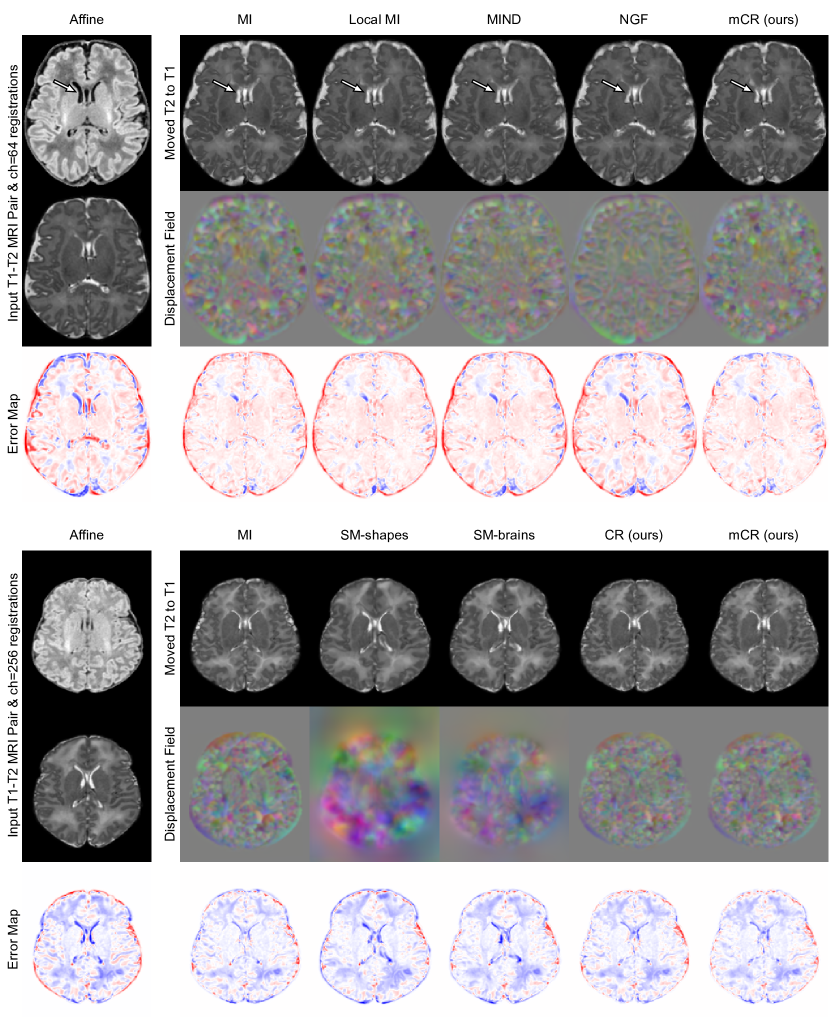

Refer to caption

Figure 2: T1w-T2w registration visualization between arbitrarily selected subjects for the (top) ch=64 and (bottom) ch=256 models. Error maps computed w.r.t. the T2w MRI of the target subject. Hypernetwork registration models are sampled with the same λ𝜆\lambda as Table 1.

Benchmarked methods. Using the same registration network with ch=64𝑐64ch=64 and ts=5𝑡𝑠5ts=5, we benchmark popular multi-modality metrics including Mutual Information (MI) (48 bins), local MI (48 bins, patch size = 9), MIND (distance = 2, patch size = 3), and normalized gradient fields, alongside the proposed mCR and CR models. We further compare against the general-purpose SynthMorph (SM)-shapes and brains models [16], by using their publicly released models and affine-aligning the images to their atlas. As SM uses ch=256𝑐256ch=256, we retrain the proposed registration models at that width. As we use public models, we cannot perform λ𝜆\lambda-conditioning and evaluation for SM. Further, as inter-subject dHCP registration can require large non-smooth deformations, we study whether a higher number of integration steps improves deformation characteristics (as in [36]) for the ch=256𝑐256ch=256 model, evaluating ts={10,16,32}𝑡𝑠101632ts=\{10,16,32\} with 323232 as default.

Results. Sample registration visualizations are provided in Fig. 2, performance scores versus λ𝜆\lambda are plotted in Fig. 3, and a study of trading-off registration accuracy for smoothness is tabulated in Table 1. We make the following experimental observations:

• (m)CR achieves higher accuracy and converges faster than baseline losses. Fig. 3 (row 1) indicates that the proposed models achieve better Dice with comparable (mCR) or better (CR) folding and smoothness characteristics in comparison to baseline losses as a function of the 17 values of λ𝜆\lambda tested. Further, Table 1 reveals that if anatomical overlap is reduced to also achieve negligible folding (defined as folds in 0.5% of all voxels [31]), CR and mCR still achieve the optimal tradeoff.

• (m)CR achieves more accurate registration than label-trained methods at the cost of lower warp regularity. While the public SM-brains model does not achieve the same Dice score as (m)CR, it achieves the third-highest performance behind (m)CR with substantially smoother deformations. We postulate that this effect stems from the intensity-invariant label-based training of SM-brains only looking at the semantics of the image, whereas our approach and other baselines are appearance based.

• Masking consistently improves results. Excluding false positive and false negative pairs from the training patches yields improved registration performance across all values of λ𝜆\lambda with acceptable increases in deformation irregularities vs. λ𝜆\lambda (Fig 3 rows 1 & 3; cols 1-3). Importantly, contrastive training without foreground masks (CR) still outperforms other baseline losses and does so with smoother warps.